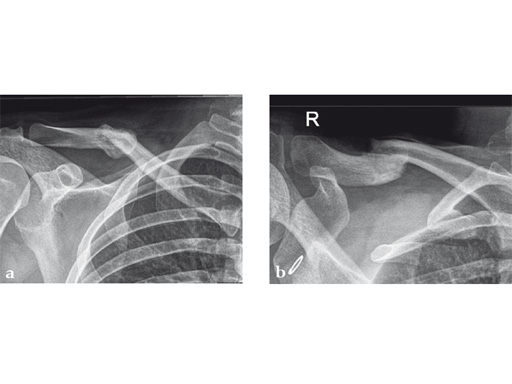

Case 1: a 30-year-old woman sustained a midshaft clavicle fracture. it healed with 2.1 cm shortening over 4 years after nonoperative treatment.

Case provided by Norbert Sdkamp and Martin Jaeger, Freiburg, Germany